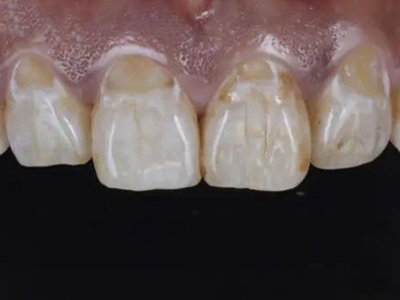

酸蚀症牙齿有黄斑轻微缺损图

酸蚀症症状较轻时,患者牙齿靠近牙根处有黄斑形成,有少量牙骨质缺损,出现较小的凹陷坑洼,该病多是长期接触外源性酸性物质或胃液反流导致。